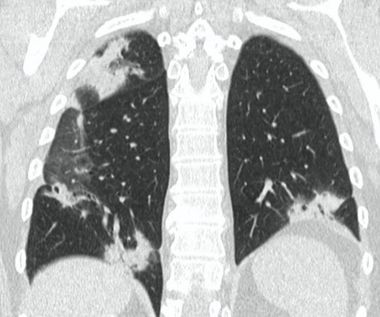

Методы лучевой диагностики применяют для выявления COVID-19 пневмоний, их осложнений, дифференциальной диагностики с другими заболеваниями легких, а также для определения степени выраженности и динамики изменений, оценки эффективности проводимой терапии.

КТ имеет высокую чувствительность в выявлении изменений в легких, характерных для COVID-19. Применение КТ целесообразно для первичной оценки состояния ОГК у пациентов с тяжелыми прогрессирующими формами заболевания, а также для дифференциальной диагностики выявленных изменений и оценки динамики процесса. КТ позволяет выявить характерные изменения в легких у пациентов с COVID-19 еще до появления положительных лабораторных тестов на инфекцию с помощью МАНК. В то же время, КТ выявляет изменения легких у значительного числа пациентов с бессимптомной и легкой формами заболевания, которым не требуется госпитализация. Результаты КТ в этих случаях не влияют на тактику лечения и прогноз заболевания при наличии лабораторного подтверждения COVID-19. Поэтому массовое применение КТ для скрининга асимптомных и легких форм болезни не рекомендуется.

Вместе с тем, комплексная оценка анамнестических, клинических и рентгенологических данных позволяет определить клинически подтвержденный случай COVID-19, маршрутизировать пациента и начать противовирусную терапию.

3. Применение лучевых методов у пациентов с симптомами ОРВИ легкой степени тяжести и стабильном состоянии пациента, возможно только по конкретным клиническим показаниям, в том числе при наличии факторов риска, при условии достаточных технических и организационных возможностей. Методом выбора в этом случае является КТ легких по стандартному протоколу без внутривенного контрастирования или РГ при ограниченной доступности КТ. Использование УЗИ в этих случаях нецелесообразно. Применение КТ исследования в сроки ранее 3 - 5 дней с момента появления симптомов заболевания является нецелесообразным.

4. Все выявляемые при лучевых исследованиях признаки, включая КТ-симптомы, не являются специфичными для какого-либо вида инфекции и не позволяют установить этиологический диагноз. Вне клинической (эпидемической) ситуации они не позволяют отнести выявленные изменения к пневмонии COVID-19 и дифференцировать их с другими пневмониями и невоспалительными заболеваниями. Данные лучевого исследования не заменяют результаты обследования на РНК SARS-CoV-2. Отсутствие изменений при КТ не исключают наличие COVID-19 и возможность развития пневмонии после проведения исследования.

15. Рекомендации по формированию описаний и оценке изменений в легких и ОГК при имеющейся/подозреваемой пневмонии COVID-19 представлены в Приложении 1.